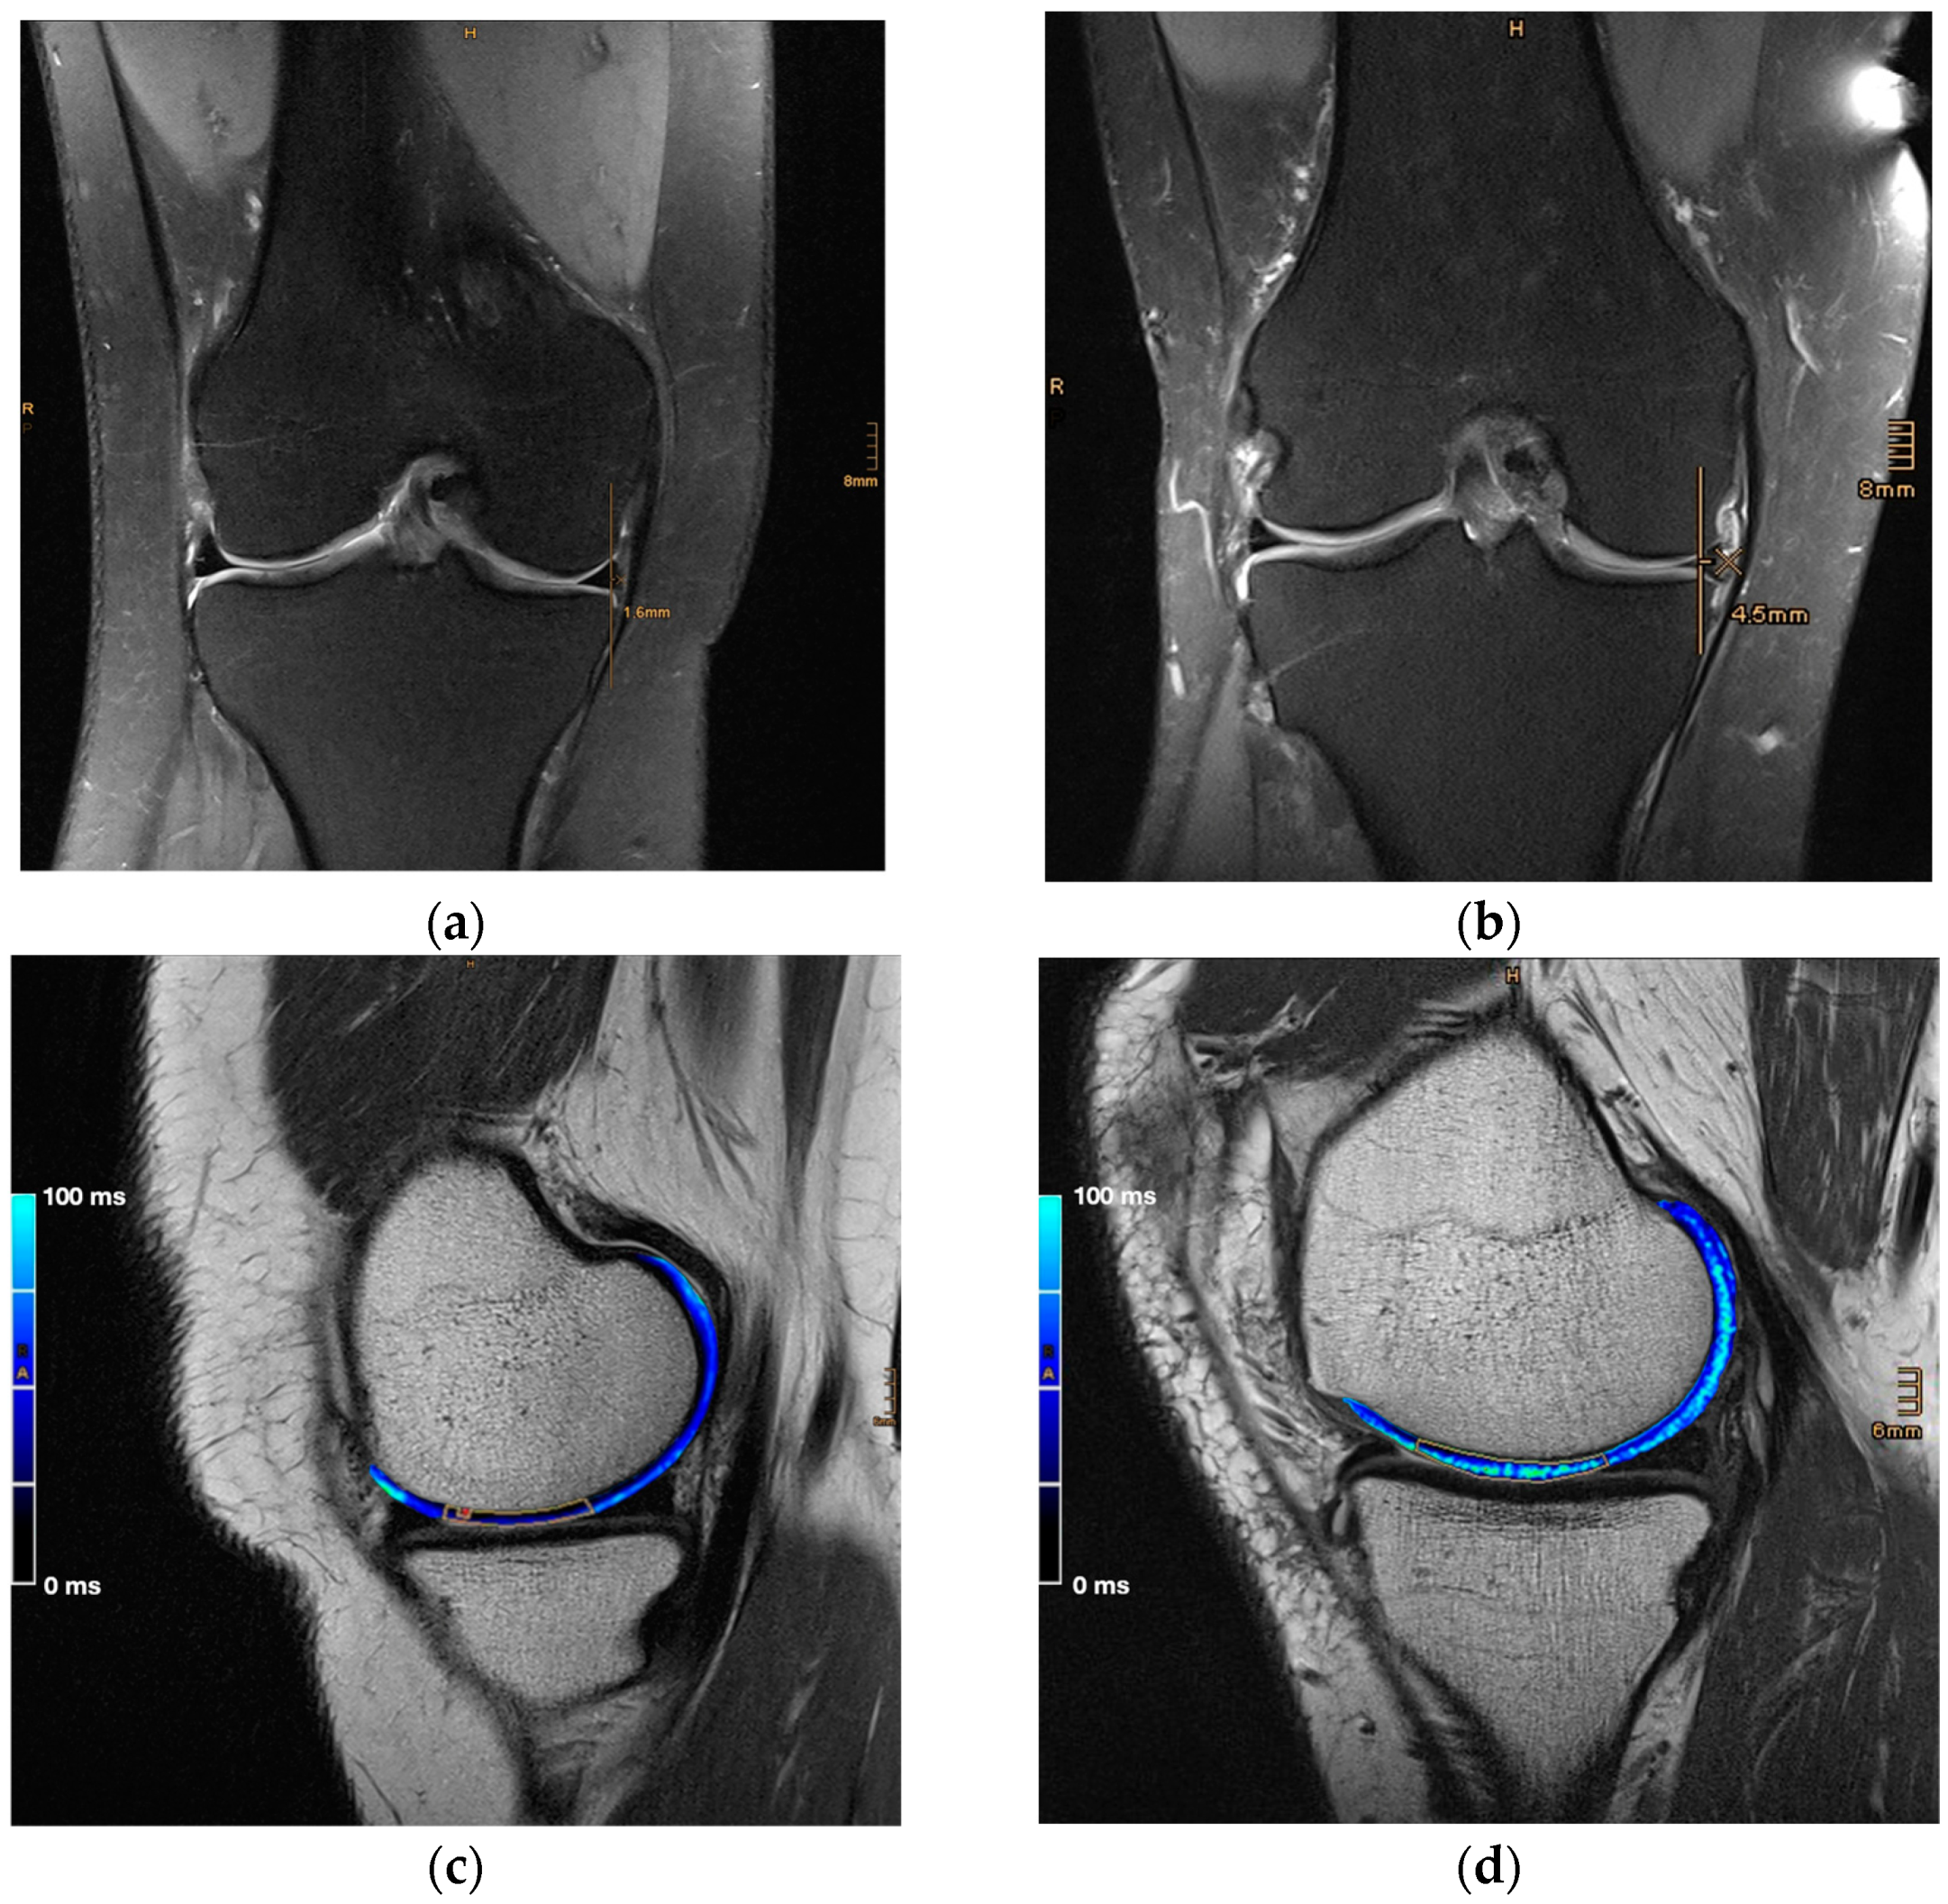

1. Introduction

2. Materials and Methods

2.2. Magnetic Resonance Imaging

2.3. Image and Data Analysis